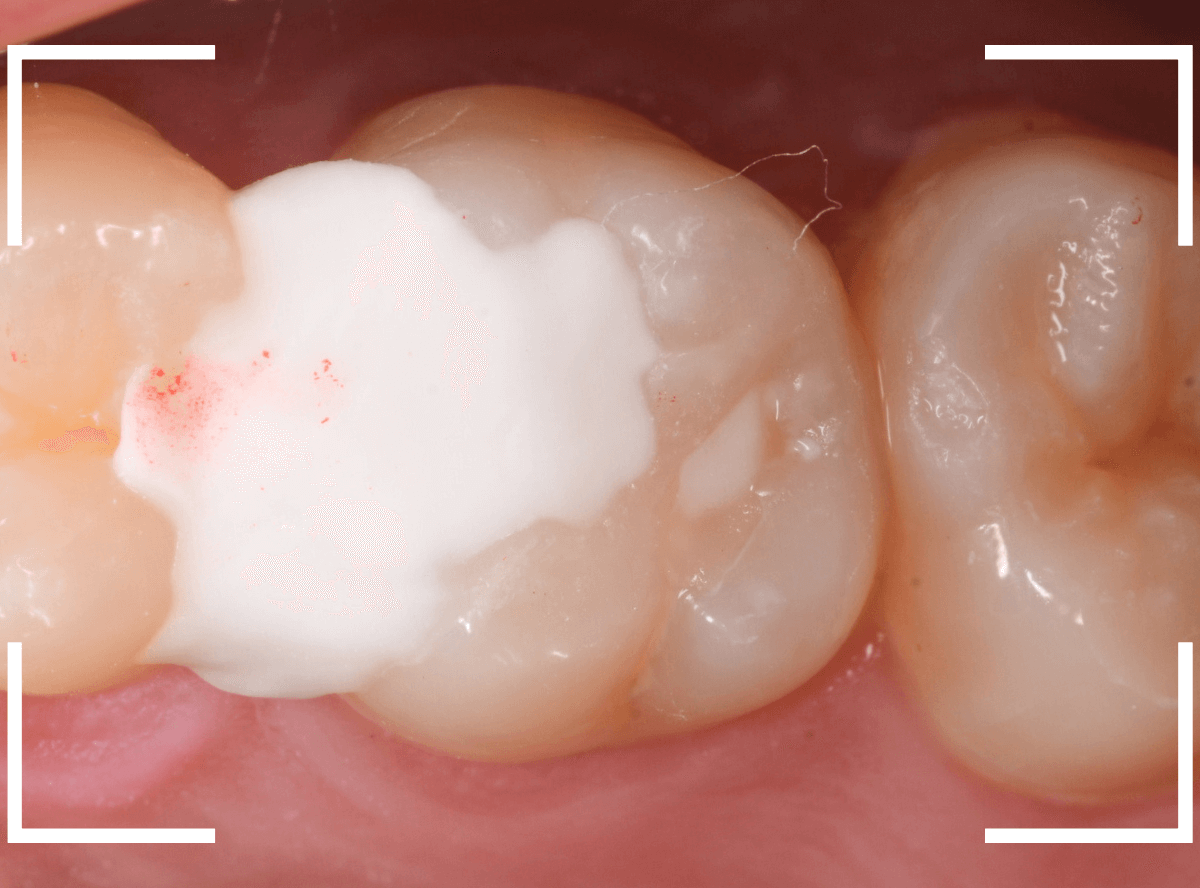

Case.5 上の一番奥の部分が深い虫歯!2

こちらも上の奥歯の奥側が虫歯になってしまった患者さんです。

本人に自覚症状はないようですが、一見して虫歯が大きそうだな、と思いました(><)

青い線が歯の神経、赤い線が虫歯です。

以前にレジン治療をした中で虫歯が進行してしまい、かなり神経に近くなってしまっていると思われます。

麻酔をして、レジンの部分を全部除去したところです。

見えづらいですが、まだ虫歯が残っているのがわかります(黒い部分)。

虫歯を全部除去したところです。

歯の1/3くらいは削る必要のある大きな虫歯でした。

神経に近い虫歯でしたので、お薬をつめてしばらく経過観察になります。